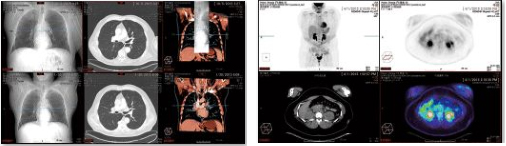

撮影画像の参照から,3Dデータの表示・解析までを実現する読影対応の「Vue PACS」は,自動位置合わせ,病変管理や,多数の解析機能で読影医をサポートします。臨床機能としては,PET/CTやCTパフュージョン解析,MRディフュージョン解析,マンモグラフィのトモシンセシス読影といった機能を搭載。効率的なPACS読影ワークフローをご提供します。